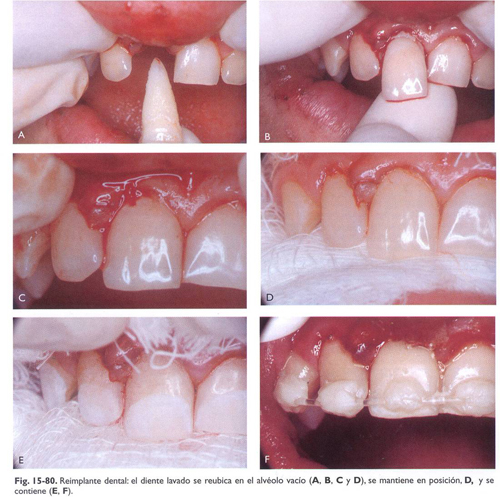

Reimplantar el diente suavemente con presión digital. Por lo general, el diente efectúa un "clic" cuando se vuelve a colocar en su posición.